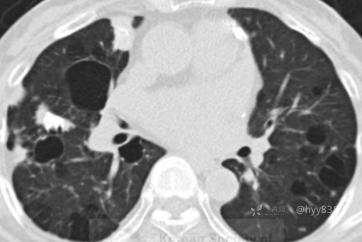

简要病史:59y/F,咳嗽伴胸部不适半年,既往史:肛门癌、SLE(系统性红斑狼疮)、狼疮性肾炎

胸部CT